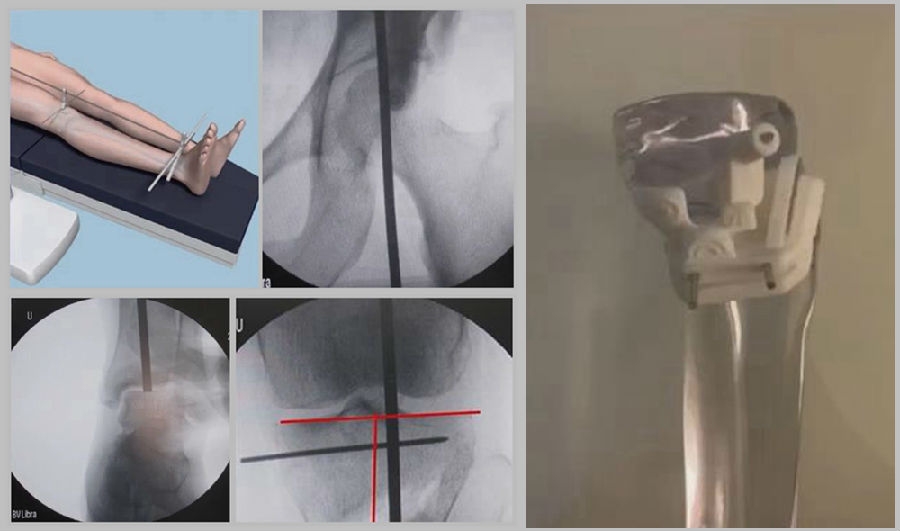

1、综合判断力线的方法

现在对于力线的判断大致通过以下几方面:①大体形态;②透视确定力线,连接股骨头中心、踝关节中心,看力线杆和膝关节中心的位置关系;③MPTA(胫骨平台关节线和胫骨侧机械轴夹角);④PSI。

(1)肢体外旋

一般来说在麻醉状态下肢体会处于外旋位,此时去测定力线的话往往需要将肢体放在旋转中立位,但是在内旋肢体的过程中会出现内翻应力,那么这种情况下判断力线会带来误差,所以通常建议大家要把手术床做一点旋转,让患肢处于自然的旋转中立位,这样再去判断力线就比较准确。

(3)力线验证未模仿负重应力

现在所谓的目标力线应该是模仿负重时的力线。做截骨时,通常会将力线轻度外移,如果没有考虑关节内畸形、韧带松弛或是软骨磨损,那么在负重时,在内侧副韧带撑开过程中,会出现力线偏移。所以要注意,手术中间在调整目标力线时,要以应力状态下为标准。

(4)拉力螺钉加压过度

拉力螺钉的过度使用可能会引起矫形位置的角度丢失。当拉力过度时,会将力线由内侧向外侧轻度拉回,使力线丢失一部分,所以切忌过度使用。